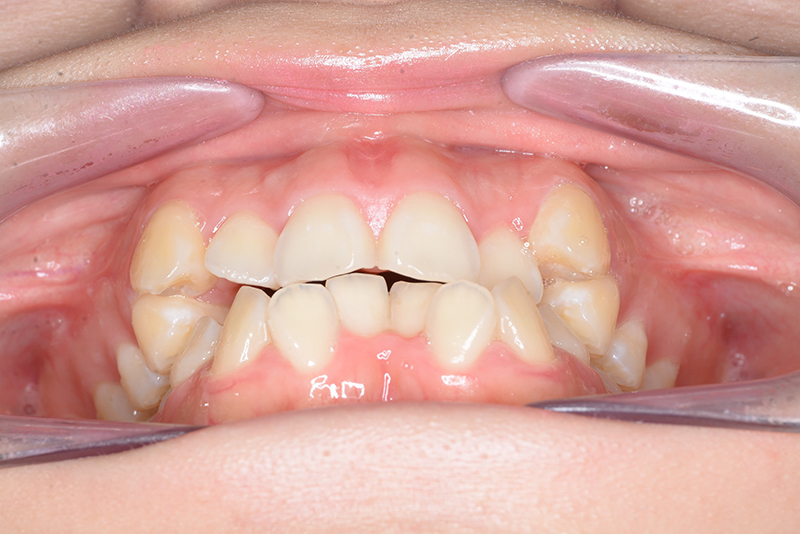

| 口腔内所見 | over jet 4.5mm、over bite 4.0mm、大臼歯関係 I級で上下顎前歯部に叢生が認められた。 |

| 批評・予后 | 叢生が大きかった影響もあり、治療期間は20ヶ月と比較的短い期間が終了できた。治療後においては口元の改善、咬合の緊密化は達成できたように思う。 |